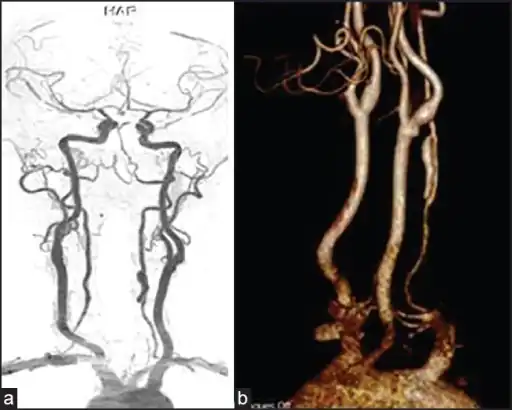

Vertebral artery dissection with focal dilatation of involved segment

Magnetic resonance angiogram of the neck vessels in a person with Ehlers-Danlos syndrome type IV; it shows a dissection of the left internal carotid artery, dissection of both vertebral arteries in their V1 and V2 segments and a dissection of the middle and distal third of the right subclavian artery. Such striking episodes of dissection are typical for this "vascular" subtype of Ehlers-Danlos syndrome.

A reconstruction of the vertebral arteries from a CT scan, seen from the front. From the bottom, V1 is from the subclavian artery to the foramina, V2 is from the foramina to the second vertebra, V3 is between the foramina until entry into the skull, and V4 is inside the skull embedded in the dura mater. They merge into the basilar artery, which then divides into the posterior cerebral artery.